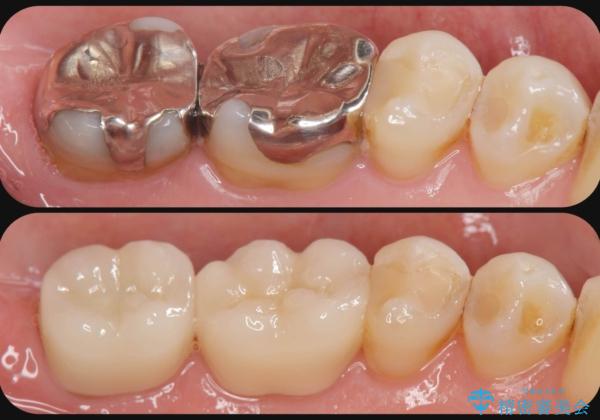

銀歯をセラミック治療で白く

- 「長年使っている奥歯の目立つ銀歯を白くしたい。」、と希望され来院されました。

銀歯を丁寧に除去し、このように銀の覆っている面積が多い場合は、インレータイプではなくより強度に優れ歯もセラミックも長持ちするジルコニアクラウンでの治療を計画します。

天然歯のような白さのセラミッククラウンで、歯本来の審美性を回復することができました。